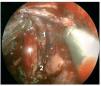

Caso clínico: Varón de 42 años de edad con paresia del VI par craneal derecho y estudios de imagen mediante resonancia magnética y tomografía computarizada craneales sugestivos de displasia fibrosa esfenoclival. Se lleva a cabo un abordaje endonasal expandido transpterigoideo completamente endoscópico, obteniéndose una amplia descompresión de las estructuras vasculonerviosas de la base del cráneo. Durante el procedimiento se utiliza neuronavegación y el canal vidiano como referencia anatómica fundamental de la carótida en su segmento lacerum.

Discusión: El AEE transterigoideo es una técnica segura y con amplio sustento en la literatura científica. En manos adecuadas, podría reducir la morbilidad asociada a los abordajes transcraneales clásicos, ya que permite un máximo potencial resectivo sobre las lesiones a tratar, con una mínima distorsión sobre las estructuras craneofaciales circundantes. Para su realización se utilizan referencias anatómicas claves como el agujero y canal del nervio vidiano. La indicación de tratamiento quirúrgico en los casos de DF de base craneal ha de establecerse en función de la presencia de sintomatología.

Case report: A 42-year-old male with right sixth cranial nerve palsy. Cranial MRI and CT showed a central skull base lesion with diagnostic suspicion of FD. Patient underwent a full endoscopic transpterygoid EEA, achieving a wide skull base neurovascular decompression. Neuronavigation and the vidian canal landmark resulted mandatory during intraoperative procedure.

Discussion: The transpterygoid EEA is a safe technique consistently supported in the literature. It may reduce the morbidity associated to the classic transcranial approaches, since it permits maximum resection with minimum craniofacial distortion. The vidian hole and canal are the landmarks used to locate and avoid injury to the lacerum segment of the carotid injury. The surgical treatment indication in FD cases must be established in symptomatic patients.